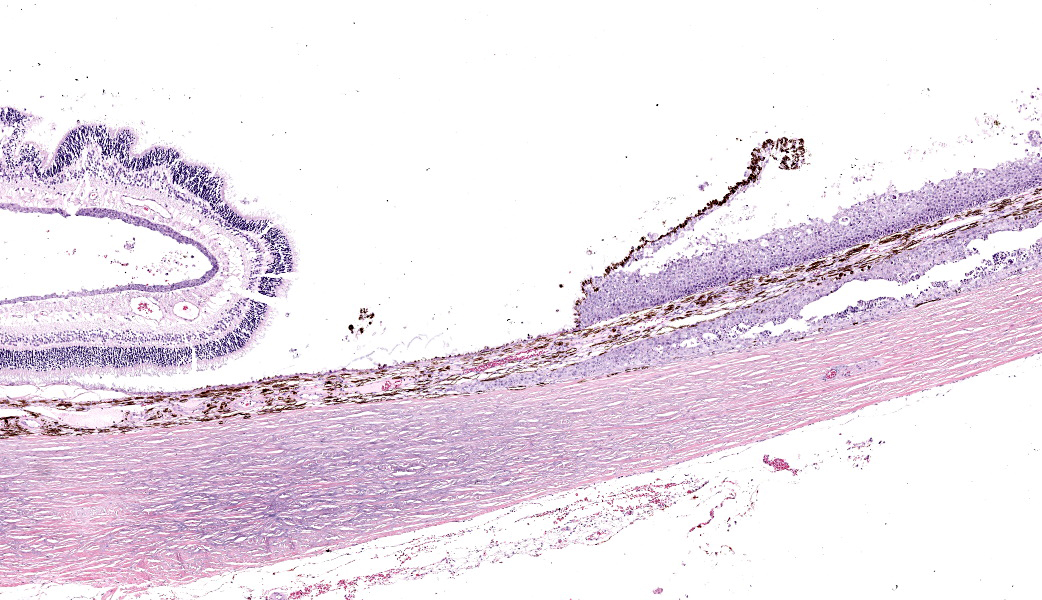

Eye: Overlying the corneal endothelium, anterior and posterior iris, portions of the lens epithelium, and the inner surface of the retina, as well as effacing and replacing the ciliary body, and occluding the drainage angle is an unencapsulated, densely cellular, infiltrative, neoplasm composed of epithelial cells arranged in broad dense cords on a moderate fibrovascular stroma. Neoplastic cells are polygonal with distinct cell borders, pronounced intercellular bridging, a moderate amount of pale eosinophilic cytoplasm, and irregularly round to vesiculate nuclei, with up to three distinct nucleoli. Anisocytosis and anisokaryosis is moderate. The mitotic rate is high with up to 12 mitotic figures per ten 40x HPF. Multifocally, neoplastic cells exhibit squamous differentiation. Near the optic nerve, the neoplastic cells invade the vascular and fibrous tunics, elevating and dissecting beneath the retinal pigment epithelium under a detached and coiled degenerate retina. At the caudal interior surface of the globe, there are numerous neutrophils admixed with abundant eosinophilic cellular and karyorrhectic debris and neoplastic cells infiltrate into the retinal vasculature.Contributor's Morphologic Diagnoses:

This case contributor gives a thorough review of intraocular neoplasms in cats, touching on many major points of discussion during review of this case. Conference participants were readily able to reach a diagnosis of metastatic carcinoma, but not all were convinced that this was a metastatic squamous cell carcinoma (SCC) due to the lack of dyskeratosis within neoplastic epithelial cells, coupled with the lack of a primary mass found during workup. The prominent intercellular bridging between the neoplastic cells was noted by all, which can be a major feature of SCC; and squamous cell carcinomas are common tumors of the feline head; however other participants felt strongly that they could not rule out a carcinoma of other origin based on histology alone. For this reason, a morphologic diagnosis of “metastatic carcinoma” was ultimately favored by participants in this case due to the lack of clear-cut evidence of a squamous cell carcinoma on the H&E.There was no argument to be found on whether this was primary or metastatic, as the histologic evidence was strongly supportive of a metastatic process (i.e., the neoplasm primarily found within the highly vascular choroid and uvea, intravascular neoplastic cell emboli, etc.). The secondary changes in the eye were also discussed and it was concluded that this eye had glaucoma secondary to the neoplasm, evidenced by the retinal ganglion cell degeneration and loss with tapetal sparing, occlusion of the drainage angles by both the neoplasm and inflammation, buphthalmia (enlarged globe, attenuated and degenerative corneal epithelium, scleral thinning), and perivascular edema of the aqueous veins that drain the trabecular meshwork of the drainage angle.